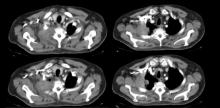

VATS is a safe approach for the treatment of a Pancoast tumor. When combined with other accesses, a VATS approach allows for radical resection, with the advantages of improved wound healing, better postoperative pain control, and decreased respiratory complications. This video presents the case of a 57-year-old patient with an adenocarcinoma of the superior sulcus in the right upper lobe, who was scheduled for surgery four weeks after induction therapy (CT and RT). VATS combined with a posterior thoracotomy approach provides the ability to assess the optimal incision and extent of rib resection. This reduces surgical trauma and provides very good results in terms of postoperative morbidity and disease-free survival.